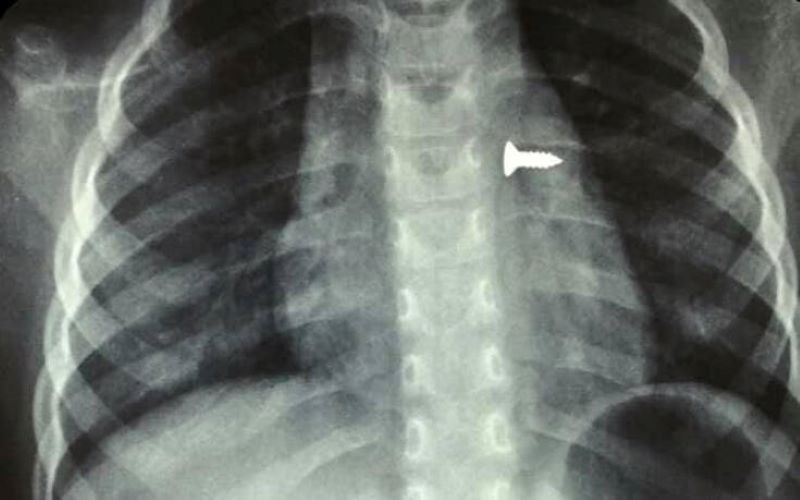

Η ζωή ενός μικρού κοριτσιού, μόλις 3 ετών, κινδύνευσε όταν κατάπια μια βίδα η οποία κατέληξε στον αριστερό της πνεύμονα. Το περιστατικό συνέβη στο Ηράκλειο της Κρήτης.

Σύμφωνα με τα όσα έκανε γνωστά ο αναπληρωτής καθηγητής ΩΡΛ της Ιατρικής Σχολής Κρήτης, Μανώλης Προκοπάκης, το κοριτσάκι μεταφέρθηκε στο νοσοκομείο και αμέσως του έγιναν ακτινογραφίες που έδειξαν πού βρισκόταν η βίδα.

Οι γιατροί άμεσα οδήγησαν τo τρίχρονο παιδί στο χειρουργείο και μετά από αρκετή ώρα κατάφεραν να αφαιρέσουν την βίδα. Ο κ. Προκοπάκης σε ανάρτησή του στα social media ανέφερε: «Πολύ επείγον χειρουργείο! Πριν από λίγο. Αφαίρεση βίδας από αριστερό βρογχικό δέντρο τρίχρονου κοριτσιού. Πολύ επικίνδυνο…».